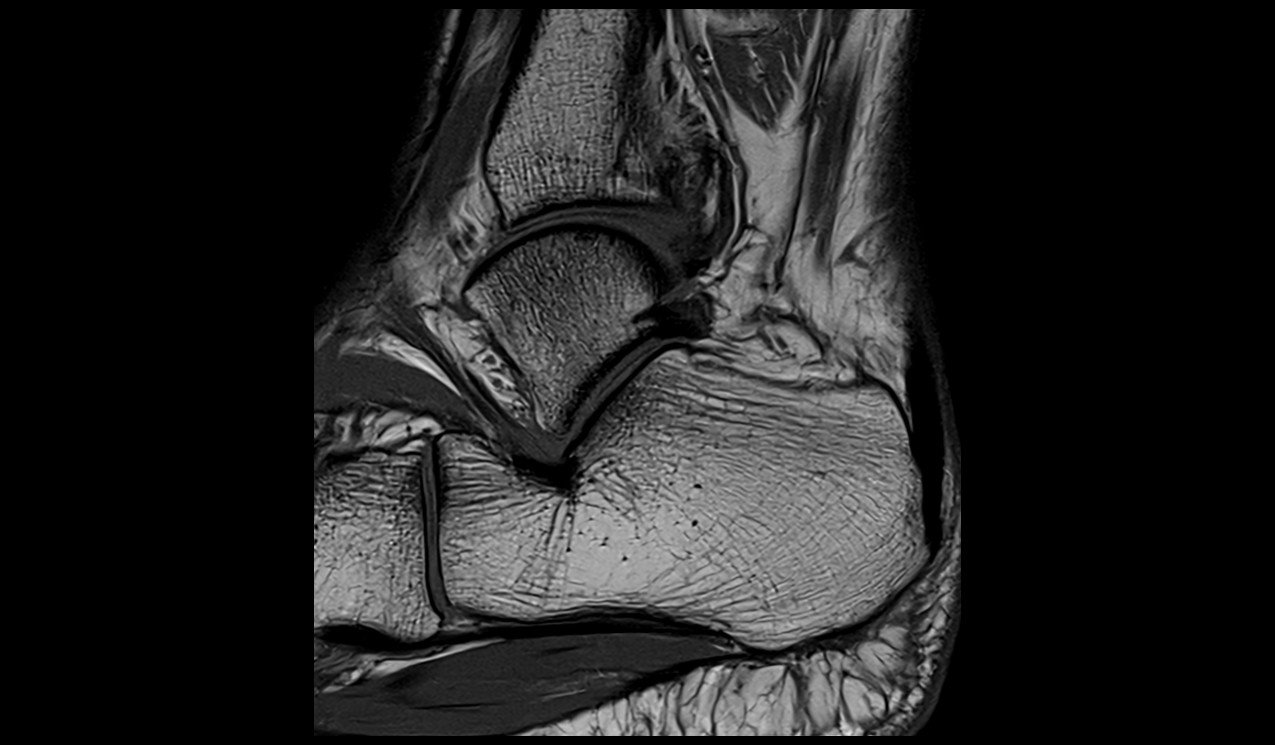

Ankle MRI sagittal t1 image